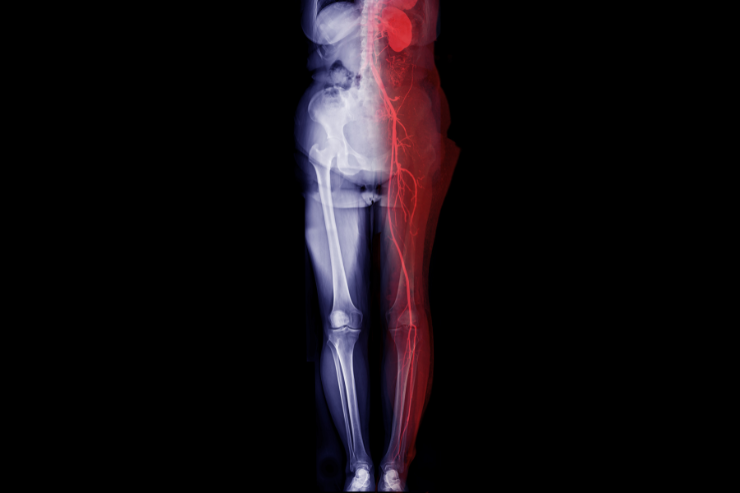

Peripheral Angiography

Peripheral Angiography is a diagnostic procedure that uses contrast dye and X-ray imaging to visualize the blood vessels in the arms and legs. It helps detect blockages, narrowing, or other abnormalities in the peripheral arteries. This procedure is crucial for diagnosing peripheral artery disease (PAD) and planning appropriate treatment to restore proper blood flow and alleviate symptoms.

Peripheral Angioplasty

Peripheral Angioplasty is a minimally invasive procedure designed to treat blockages or narrowing in the peripheral arteries, typically in the legs. A balloon is inserted through a catheter and inflated at the site of the blockage to widen the artery and improve blood flow. This procedure helps alleviate symptoms of peripheral artery disease (PAD) and enhances mobility.